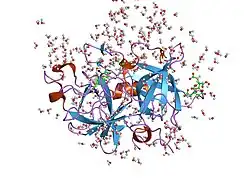

Urokinase is a 411-residue protein, consisting of three domains: the serine protease domain (consisting of residues 159–411), the kringle domain (consisting of residues 50-131), and the EGF-like domain (consisting of residues 1-49). The kringle domain and the serine protease domain are connected by an interdomain linker or connecting peptide (consisting of residues 132–158). Urokinase is synthesized as a zymogen form (prourokinase or single-chain urokinase), and is activated by proteolytic cleavage between Lys158 and Ile159. The two resulting chains are kept together by a disulfide bond between Cys148 and Cys279.[9]

The most important inhibitors of urokinase are the serpins plasminogen activator inhibitor-1 (PAI-1) and plasminogen activator inhibitor-2 (PAI-2), which inhibit the protease activity irreversibly. In the extracellular matrix, urokinase is tethered to the cell membrane by its interaction to the urokinase receptor.